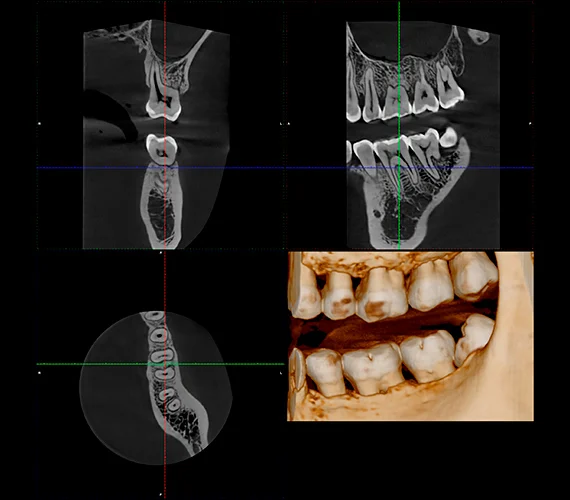

Mode endodontique pour une imagerie ultra-précise

Grâce à sa résolution endodontique de 75 µm, le Planmeca Viso® G1 permet d’observer avec précision les moindres détails anatomiques. Ses images extrêmement nettes en font un outil idéal pour les examens endodontiques ou tout cas nécessitant une visualisation minutieuse de la zone d’intérêt. La qualité d’image peut être encore améliorée grâce à Planmeca NOA™, un outil d’optimisation du bruit basé sur l’intelligence artificielle.